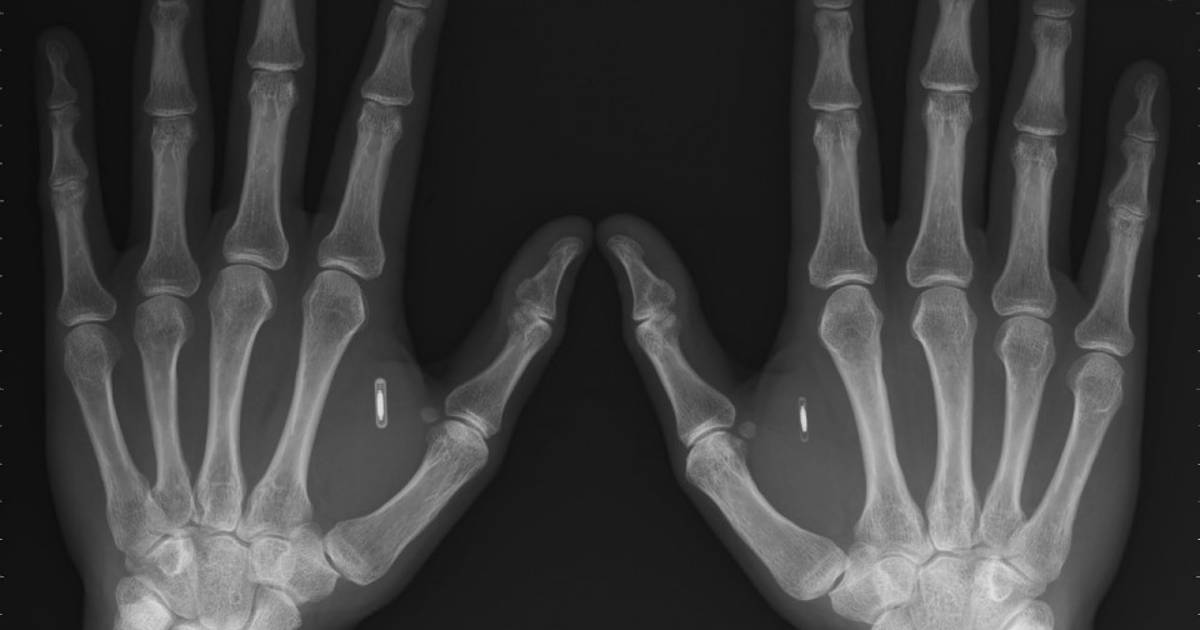

Casi cualquier parte de tu cuerpo puede usarse como forma de identificación. La disciplina que se encarga de medir un rasgo tuyo para darte entrada a ciertos datos se llama biometría.

Las principales formas implementadas o estudiadas incluyen reconocimiento de huellas dactilares, rostro, iris, voz y geometría de la mano.

Muchas otras modalidades se encuentran en distintas etapas de desarrollo y evaluación como el DNA, las orejas, la forma de escribir o caminar, las venas e incluso el olor.